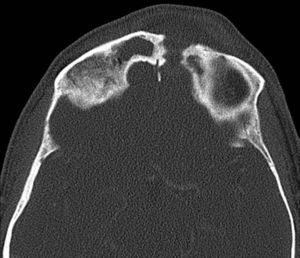

Se solicitó una tomografía computarizada (TC) facial donde se pudo observar una ocupación completa del seno frontal por material de partes blandas con engrosamiento mucoso de celdillas etmoidales, solución de continuidad de grosor completo en la vertiente izquierda del seno frontal que comunica el espacio intra y extracraneal, identificándose colecciones hipodensas en ambos espacios con realce periférico compatibles con abscesos. En localización intracraneal extraaxial se observaron 2 abscesos, uno frontal izquierdo de 3×2,4×5,1cm y otro adyacente frontal derecho de 1,4×9×4,5cm. En tejido celular subcutáneo se observó un absceso de 4,6×1,4×3,3cm que se extendía hacia la región nasal y palpebral izquierda (fig. 2).